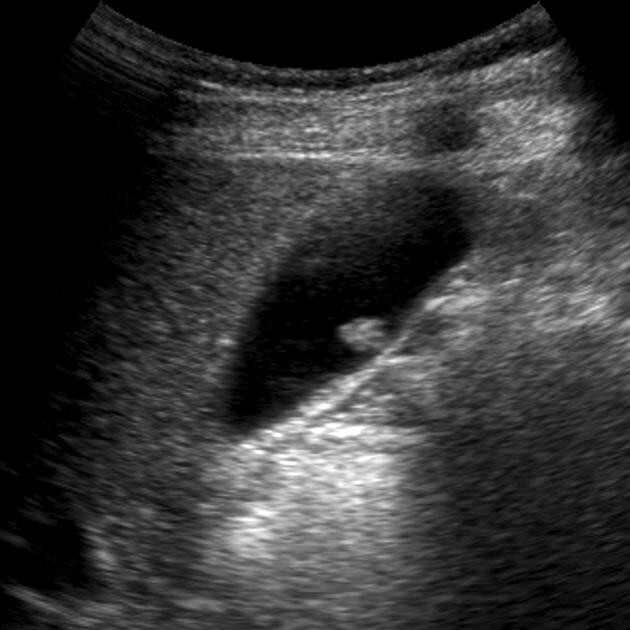

2. 담낭 용종의 초음파 소견

복부 초음파는 담낭 용종 진단의 가장 기본적인 도구입니다. 다음과 같은 특징이 대표적입니다.

- 내강 내 고정된 에코음영: 체위 변화에도 움직이지 않음

- 후방음영 없음: 담석과 구별됨

- 작고 둥근 돌출 병변: 대부분 5mm 이하의 콜레스테롤 용종

콜레스테롤 용종은 밝은 에코를 가진 작고 둥근 다발성 병변으로 보이며, 초음파에서 가장 흔하게 관찰됩니다. 반면, 무경성(sessile) 용종이나 1cm 이상 크기의 병변은 선종 가능성을 의심할 수 있어 정밀 평가가 필요합니다 [1].